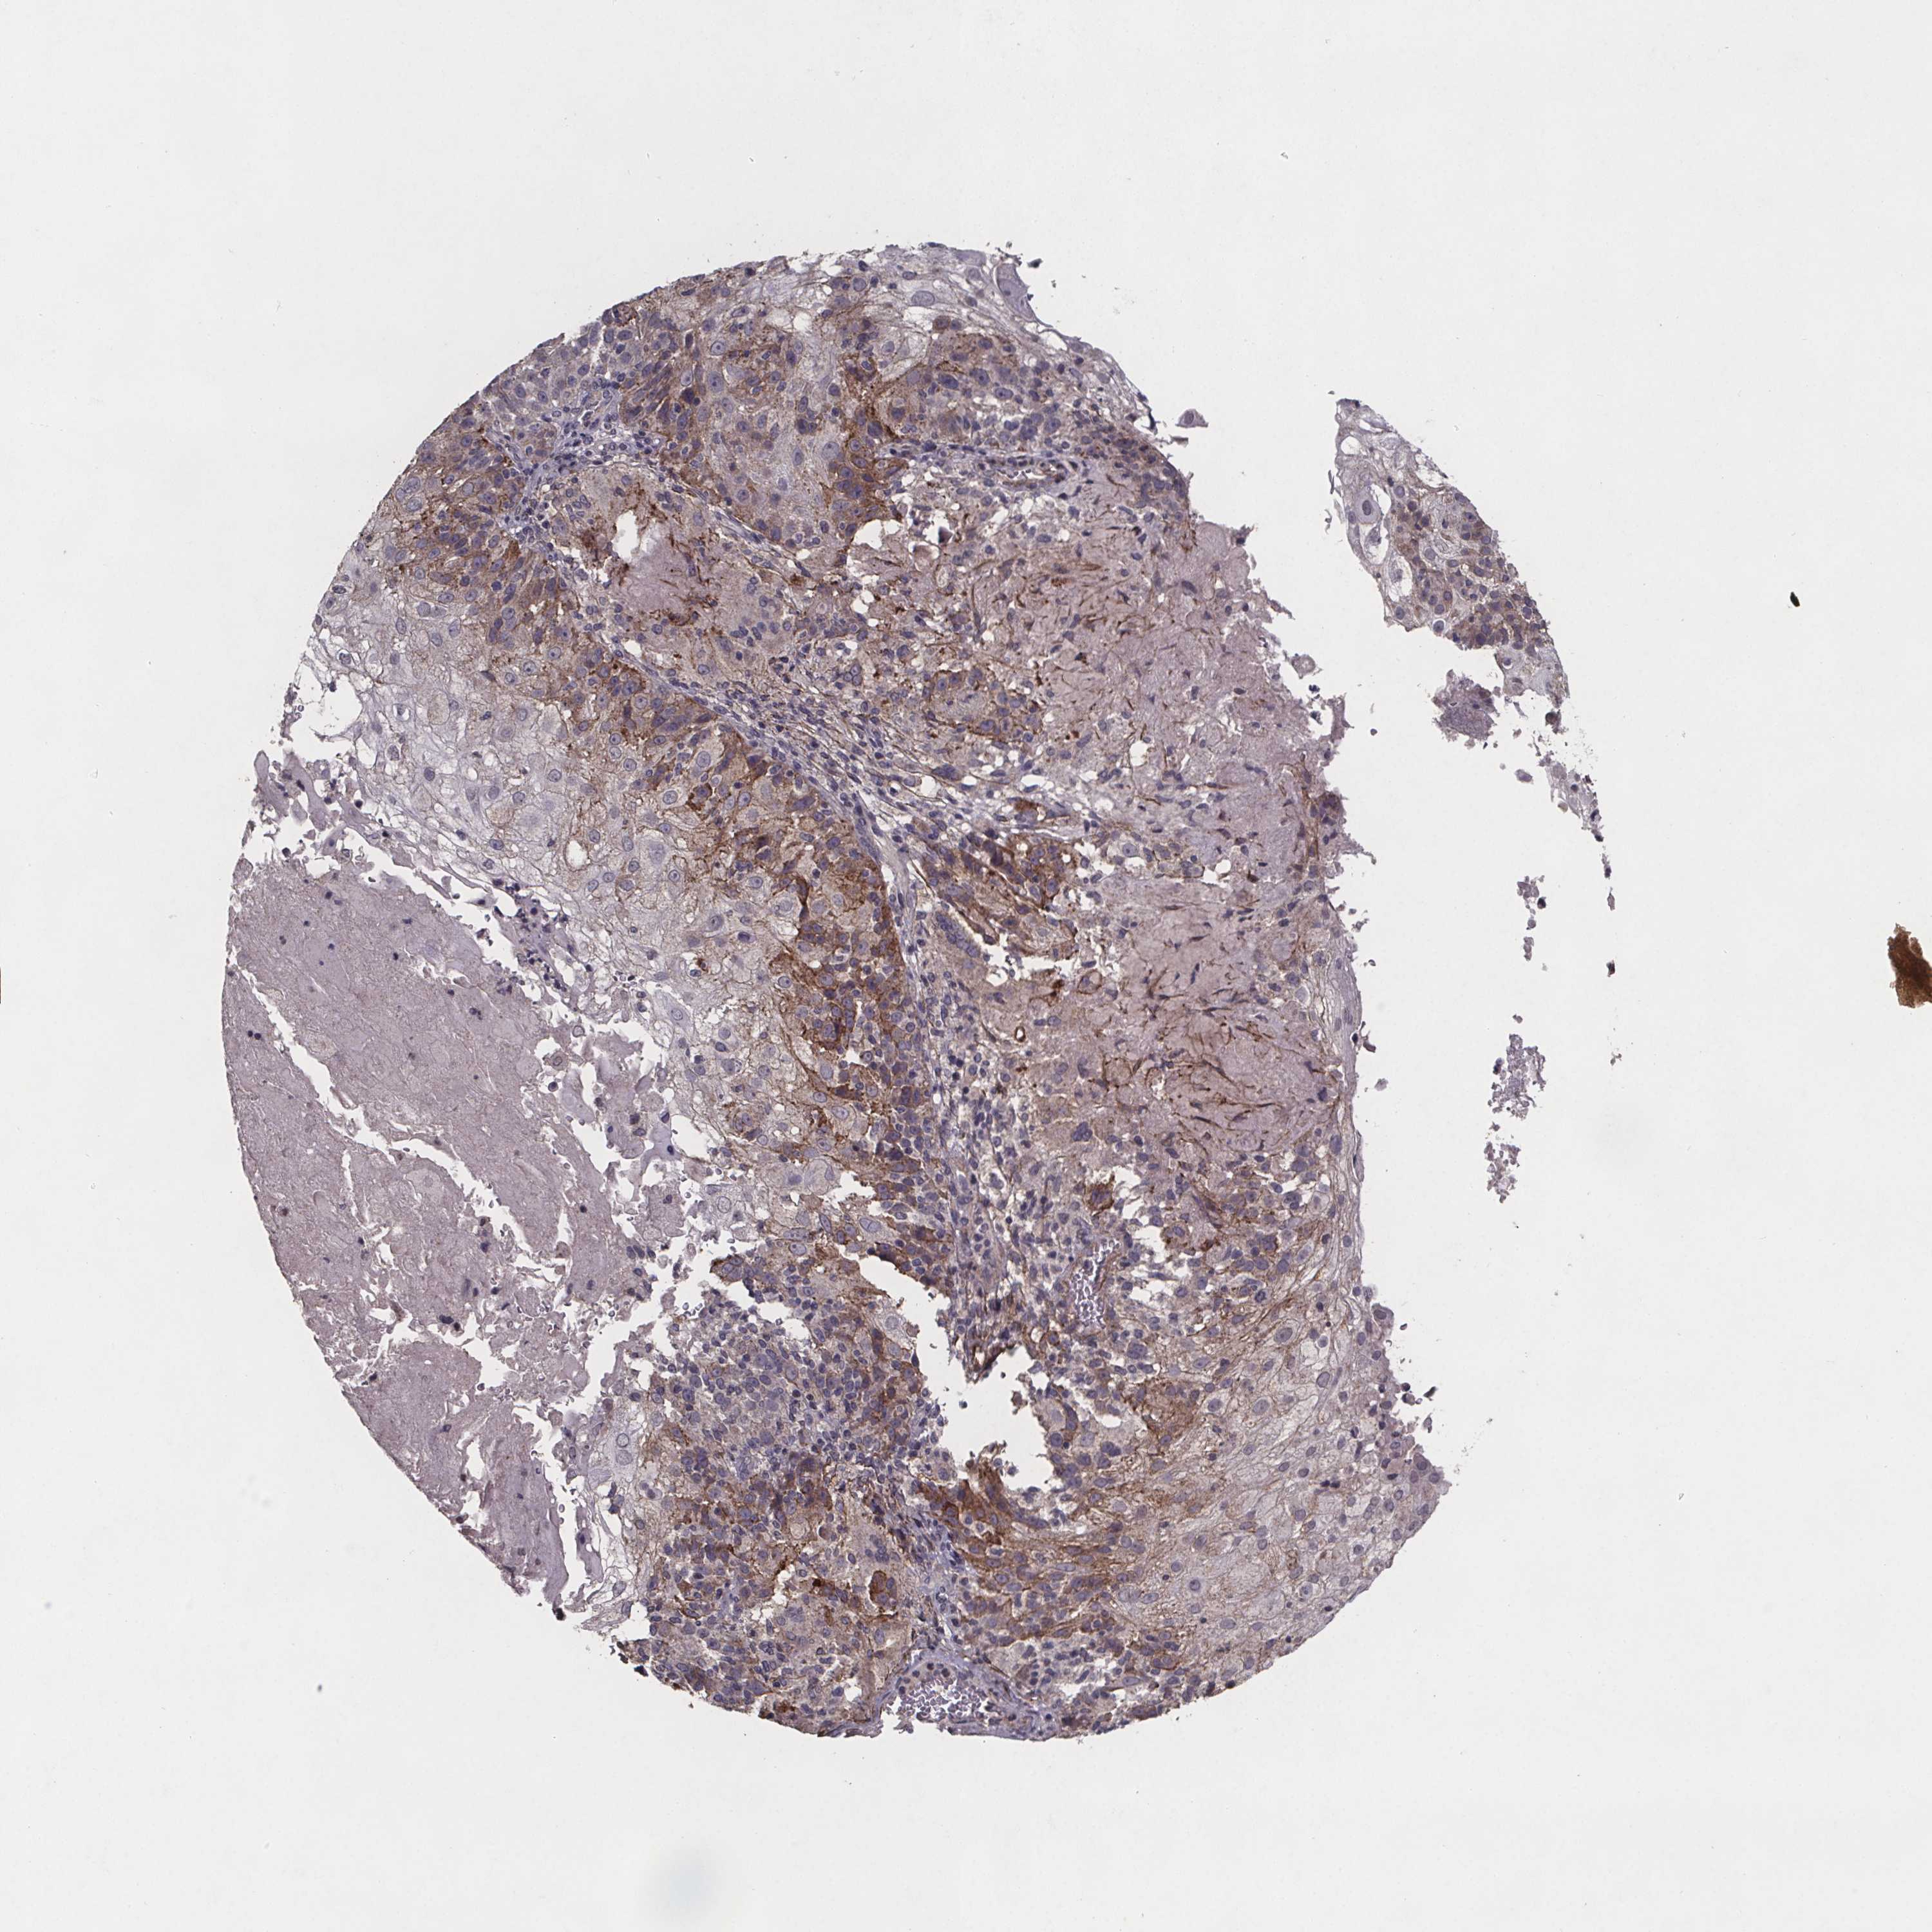

SKIN CANCER - Protein expressioni

A mouse-over function shows sample information and annotation data. Click on an image to view it in a full screen mode. Samples can be filtered based on level of antibody staining by selecting one or several of the following categories: high, medium, low and not detected. The assay and annotation is described here.

Antibody stainingi

Antibody staining in the annotated cell types in the current human tissue is reported as not detected, low, medium, or high, based on conventional immunohistochemistry profiling in selected tissues. This score is based on the combination of the staining intensity and fraction of stained cells.

Each image is clickable and will lead to virtual microscopy that enables deeper exploration of all samples and also displays staining intensity scores, fraction scores and subcellular localization as well as patient and tissue information for each sample.

Antibody CAB070159

Staining

High

Medium

Low

Not detected

Intensity

Strong

Moderate

Weak

Negative

Quantity

>75%

75%-25%

<25%

None

Location

Nuclear

Cytoplasmic/membranous

Cytoplasmic/membranous,nuclear

Basal cell carcinoma

Squamous cell carcinoma, NOS